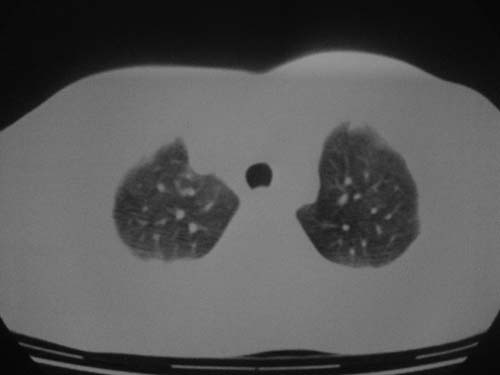

这是第五天拍的ct,纵隔窗我没都传,实在是太费时,请教各位老师,此病人有肺水肿吗?帮忙分析一下